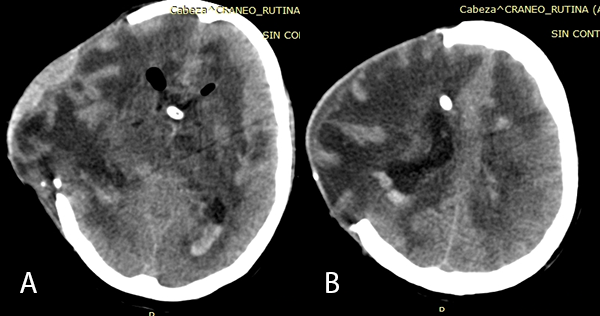

Se realizó la neuroendoscopía utilizando una óptica de 0 grados, de 30 cm. ingresando por el lóbulo frontal derecho. Inmediatamente al ingreso de la óptica se evidenciaron múltiples adherencias intra ventriculares. El foramen de Monro se encontraba parcialmente obstruido por una adherencia, además el epéndimo presentaba coloración amarillenta y las adherencias se encontraban difusamente en los ventrículos. Se intentó realizar una extracción de las membranas, pero se encontraban adheridas firmemente a las paredes ventriculares. (Imagen 4). Se realizó la fenestración del Septum Pellúcidum, con colocación de una nueva DVE, por lo que el paciente presentó mejoría clínica e imagenológica (Imagen 5).

Imagen 5: (A) y (B) TEM cerebral sin contraste en cortes axiales post fenestración y colocación de nuevo DVE: se evidencia disminución de la asimetría ventricular y disminución de protrusión por defecto óseo craneal.